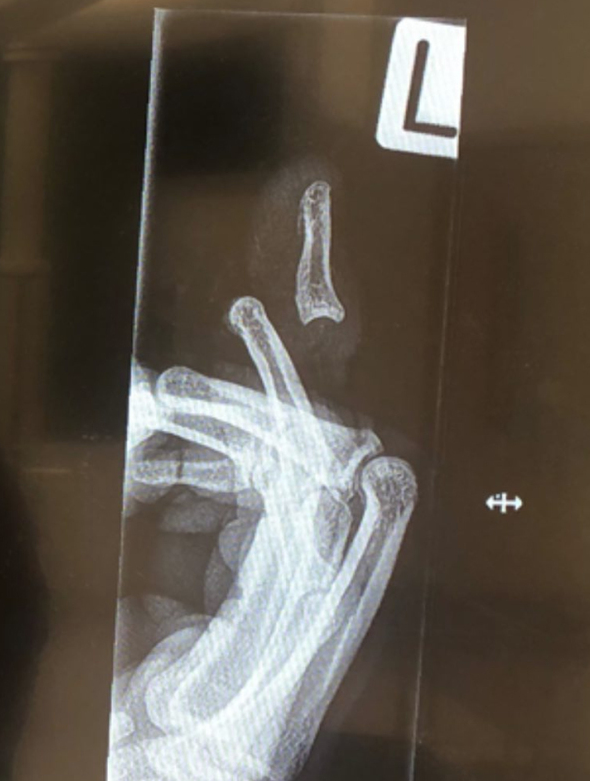

Зірка крикету Джиммі Нішам отримав жахливу травму пальця під час матчу регулярного чемпіонату Нової Зеландії.

Спортсмен опублікував фотографію пальця в Instagram, але травма виявилася настільки серйозною, що соціальна мережа була змушена розмістити на зображенні попередження про "конфіденційній контент".

Втім, після перенесеної операції палець, за словами Нішама, став "як новенький". Спортсмен сподівається повернутися до тренувань найближчим часом.

"Мені провели невелику процедуру, щоб переконатися, що мій палець все ще в хорошій формі. На щастя, все добре. Моя мета - повернутися в лад на початку лютого", - сказав Нішам.